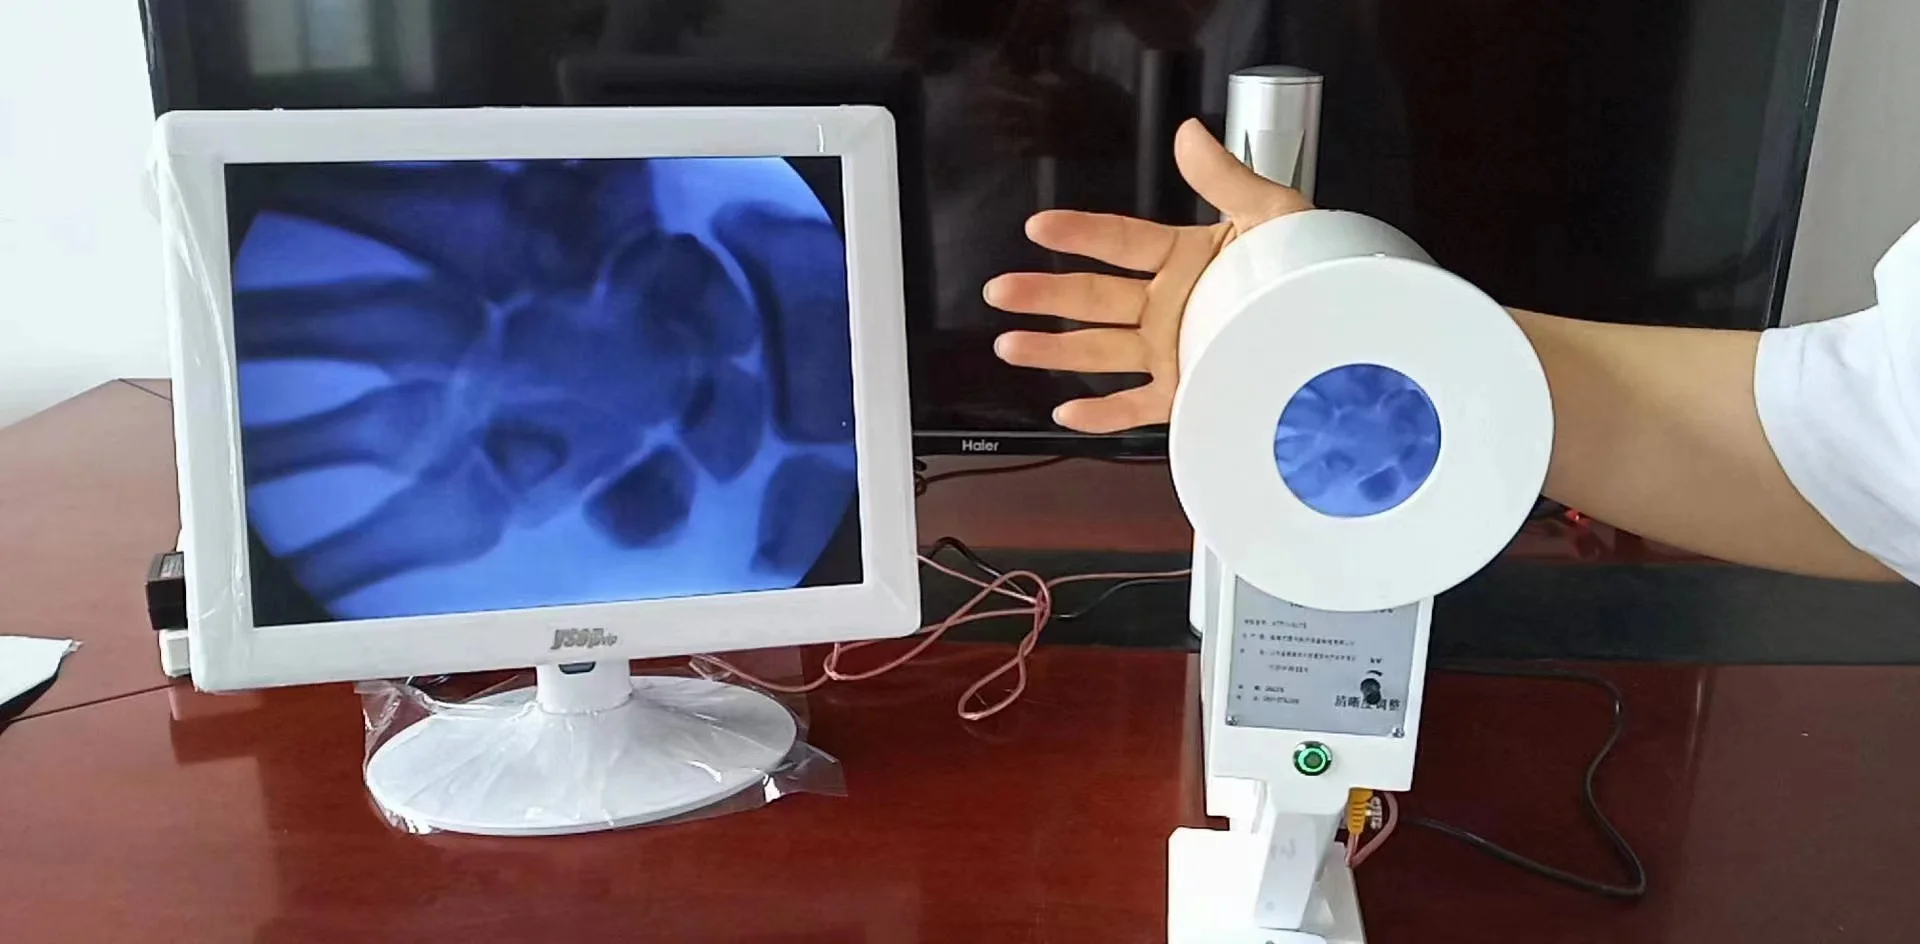

Здоровье на первом месте: диагностика и лечение через рентгеноскопию конечностей